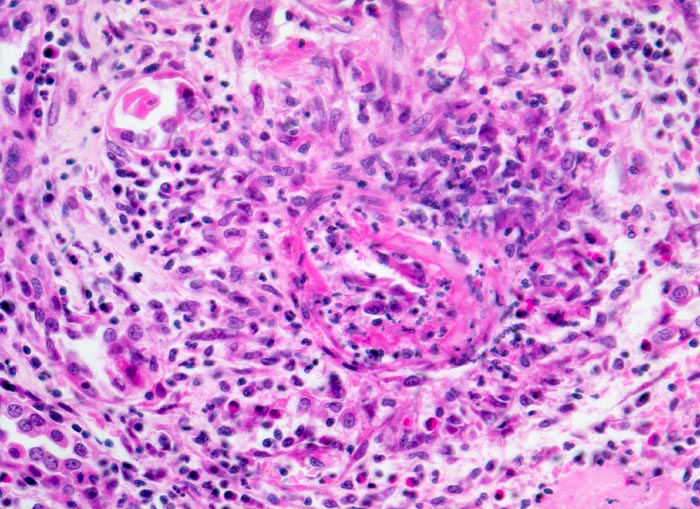

Morphologische Merkmale:

• Unauffällige Glomerula.

• Grössere intrarenale Arterien mit teils zirkulären, teils segmentalen, transmuralen fibrinoiden Gefässwandnekrosen und gemischtem transmuralem Entzündungsinfiltrat.

• Gefässveränderungen unterschiedlichen Alters (frische Nekrosen, Granulationsgewebsbildung, Narben).

• Frische Tubulusnekrosen (abgeblasste Kerne) im Versorgungsbereich der entzündeten Arterien.